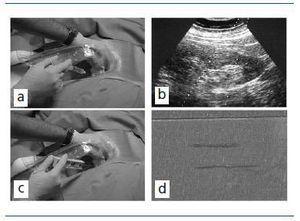

La biopsia renal percutánea dirigida con ecografía en tiempo real es la técnica de elección9,10 y permite obtener material suficiente en más del 95% de los casos. Es conveniente que se sigan los pasos de una vía clínica para evitar la variabilidad y coordinar a los profesionales implicados: médicos, ATS y auxiliares. La biopsia debe realizarse por un médico experimentado y nunca por especialistas en formación no supervisados.9 La polémica sobre quién debe ser el protagonista del procedimiento (nefrólogo, radiólogo o urólogo) no está cerrada11 y depende de la organización, experiencia y disponibilidades de cada hospital. Lo realmente importante es que el nefrólogo participe de forma activa y que la biopsia sea segura y eficaz.

La figura 3 resume los pasos más importantes, que resumimos a continuación.10,12 El paciente debe estar en ayunas y tener canulada una vía venosa periférica. Debe permanecer en decúbito prono y colaborar con los movimientos respiratorios. Es conveniente administrar atropina sc y un ansiolítico oral para mejorar la colaboración y evitar reacción vagal. Hay que localizar el riñón mediante ecografía, especialmente el polo inferior del riñón izquierdo donde habitualmente es más fácil la punción con menos riesgos de lesionar otros órganos. Posteriormente, hay que administrar anestesia local y desinfectar la zona de punción. Las sondas ecográficas con adaptador para la aguja permiten la visualización del riñón en tiempo real y se puede guiar la progresión de la aguja. La punción a ciegas no es recomendable aunque se haya localizado la posición renal en ecografía previa. No obstante, a veces no se dispone de esta posibilidad y hay que guiarse por métodos indirectos, como las oscilaciones de una aguja de punción lumbar con los movimientos respiratorios al puncionar la cápsula renal. Las denominadas pistolas con disparo automático que llevan incorporadas agujas ecogénicas de 14-18 G son las más sencillas de utilizar, con menos riesgos y similar eficacia diagnóstica comparadas con las antiguas agujas manuales tipo TruCut o la modificada de Menghini.9,13,14 En nuestra experiencia, la aguja Monopty (Bard®) es muy fácil de utilizar y obtiene material en la mayoría de las ocasiones. Por supuesto, hay que extremar las medidas de precaución universales para evitar contagios procedentes de pacientes infectados por virus C, VIH, B u otros agentes. Es conveniente extraer dos cilindros renales y llevarlos inmediatamente al Laboratorio de Anatomía Patológica, e identificar si hay glomérulos suficientes, es decir, más de cinco glomérulos en cada uno de ellos, idealmente diez o más, ya que las muestras con menos glomérulos no son capaces de detectar lesiones focales. En caso de que no haya material, se debe repetir la punción siempre que el paciente pueda colaborar. No es recomendable sobrepasar las cuatro punciones. En los casos donde hay que trasladar los cilindros a otro hospital, hay que organizar con detalle la forma de transporte. Para que la biopsia sea útil, es esencial el transporte del material al Laboratorio de Anatomía Patológica, el muestreo y preservación del material, la elección de las técnicas especiales y, por supuesto, el rigor y la exhaustividad en el informe del patólogo.15,16 Desgraciadamente, no siempre se guarda muestra o no se puede hacer estudio con microscopio electrónico y algunas biopsias, al menos en nuestro país, se estudian de forma incompleta. Según los datos del Registro de Glomerulonefritis, sólo un 18% de las biopsias tiene estudio completo, mientras que la mayoría, el 75%, tiene informe convencional con óptico e inmunofluorescencia. Aunque muchas enfermedades renales no requieren estudio ultraestructural, otras entidades sólo pueden ser diagnosticadas mediante esta técnica. Una vez finalizada la biopsia, es conveniente que se inicie la cumplimentación de un formulario con los datos clínicos y analíticos, como control interno de las biopsias de cada Servicio. También puede servir para enviar los datos al Registro de Glomerulonefritis de la SEN, cuando se tenga el diagnóstico definitivo.

Figura 3. Biopsia renal percutánea: a) anestesia local de la zona de punción; b) localización del riñón con ecografía y visualización de la zona de progresión de las agujas para visualizar en tiempo real su progresión y zona de punción; c) utilización de pistola au